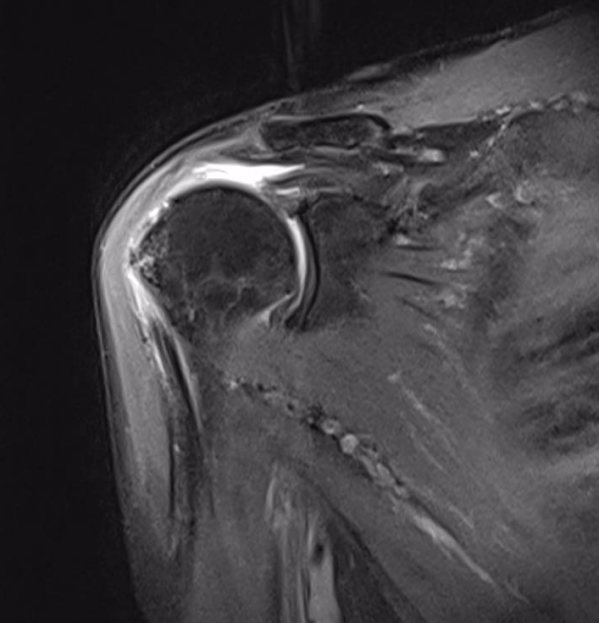

患者党某,1 年前无明显诱因出现右肩关节疼痛,尤其肩关节上举外展疼痛剧烈,右手不能搭到左肩上,近日疼痛逐渐加重生活受到严重影响,遂来延安市中医医院运动医学科求诊。

北京大学第三医院驻延专家林霖教授、运动医学科主任庞军、副主任张志宇、刘博旭医师团队综合评估了患者病情,尊重患者及家属意愿,为患者制定了周密的微创手术治疗方案。

由于巨大肩袖撕裂手术难度大, 对缝合及重建的技术要求高,需要扎实的手术经验及操作技术才能完成。手术中手术团队默契配合,在关节镜下经充分松解后行肩袖修补,手术顺利完成,患者现恢复情况良好。